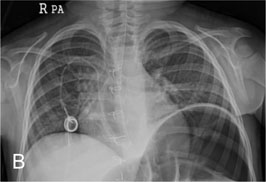

Fig. 1-A

Remained TIVD with vegetation within RA after TIVD removal operation on echocardiogram

Fig. 1-A Remained TIVD with vegetation within RA after TIVD removal operation on echocardiogram